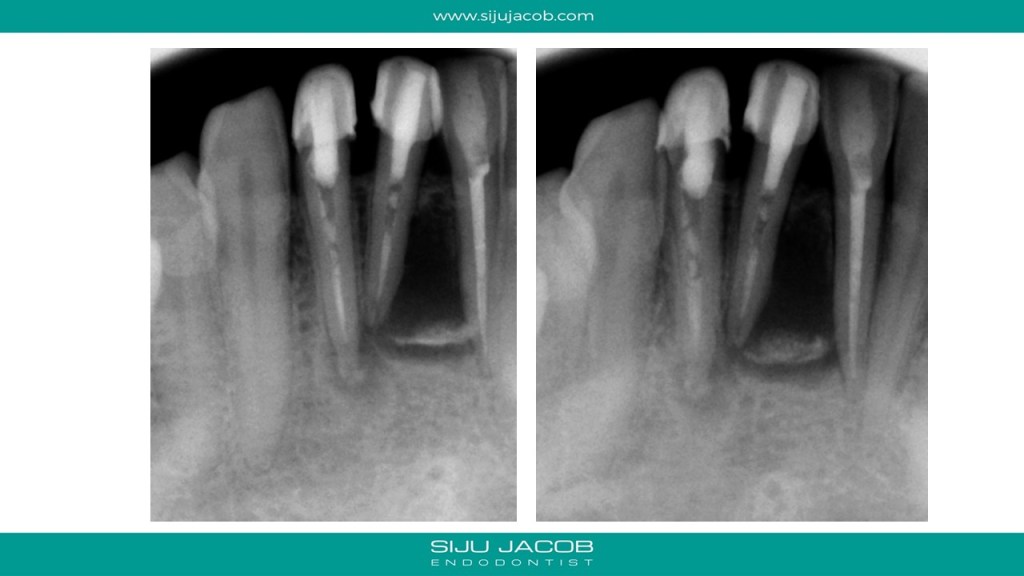

This case seemed to be responding well to conventional treatment. There wasn’t any drainage, so I obturated. The patient kept getting pain in the labial surface. So, we decided to do de-compression. The tooth reponded well to decompression and we saw very good healing at 6-months post de-compression. I saw this patient again 2 years later and someone meanwhile had gone and placed joint crowns on these teeth. Oh well….